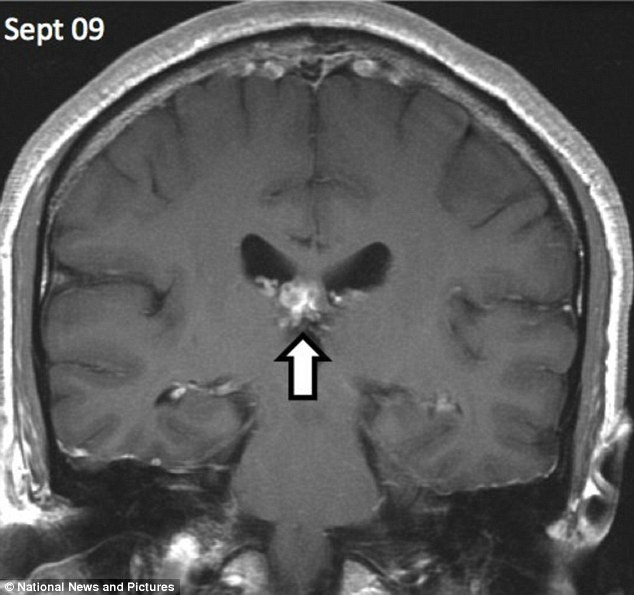

Hình chụp X-quang của một người đàn ông cho thấy anh ta đã bị một con sán dây dài 1cm đào sâu tới 5cm vào não từ trái qua phải.

Sán dây dài 1cm sống trong não người đàn ông trong suốt 4 năm ảnh 1Hình chụp não bệnh nhân bị sán dây xâm nhập. (Nguồn: DM)